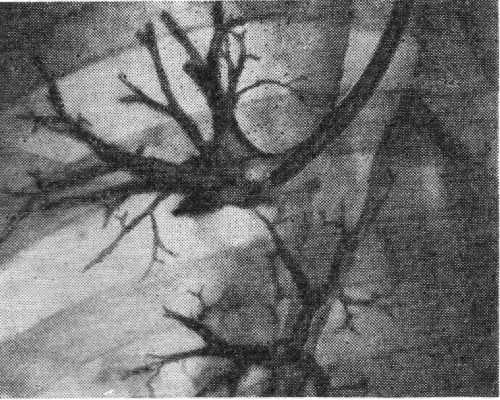

Наибольшее применение получили чрезгортанные способы Б. с введением катетера трансназально или трансорально. Наиболее распространена, проста и доступна методика трансназального введения катетера (рис. 1). При трансоральном чрезгортанном способе катетер вводят через бронхоскоп, интубационную трубку (лучше двухпросветную) или двухпросветную трубку Карленса. Эти методические приемы используют при поднаркозной Б. с управляемым дыханием. Двухпросветная интубационная трубка предотвращает затекание контрастного вещества в противоположное легкое, а двухпросветная трубка Карленса, использование которой возможно и под местной анестезией, позволяет к тому же аспирировать содержимое бронхов до п после контрастирования.

Для прицельного заполнения бронхов применяют специальные наборы полуупругих резиновых зондов, кончики которых изогнуты под различными углами, соответствующими углам отхождения отдельных бронхов (зонды Метра). Шагом вперед явилась идея управляемых с помощью нити катетеров (катетеры Розенштрауха, Розенштрауха — Смулевича), к-рым в нужный момент под рентгеноскопическим контролем можно придать необходимый изгиб (рис. 2). При потягивании за выведенную наружу нитку кончик катетера может быть изогнут и путем вращения направлен в тот или иной бронх (рис. 3). В последние годы в практику входят управляемые катетеры, изготовленные из прозрачных пластических масс, содержащих рентгеноконтрастное вещество, сконцентрированное в виде тонкой нити в стенке катетера.